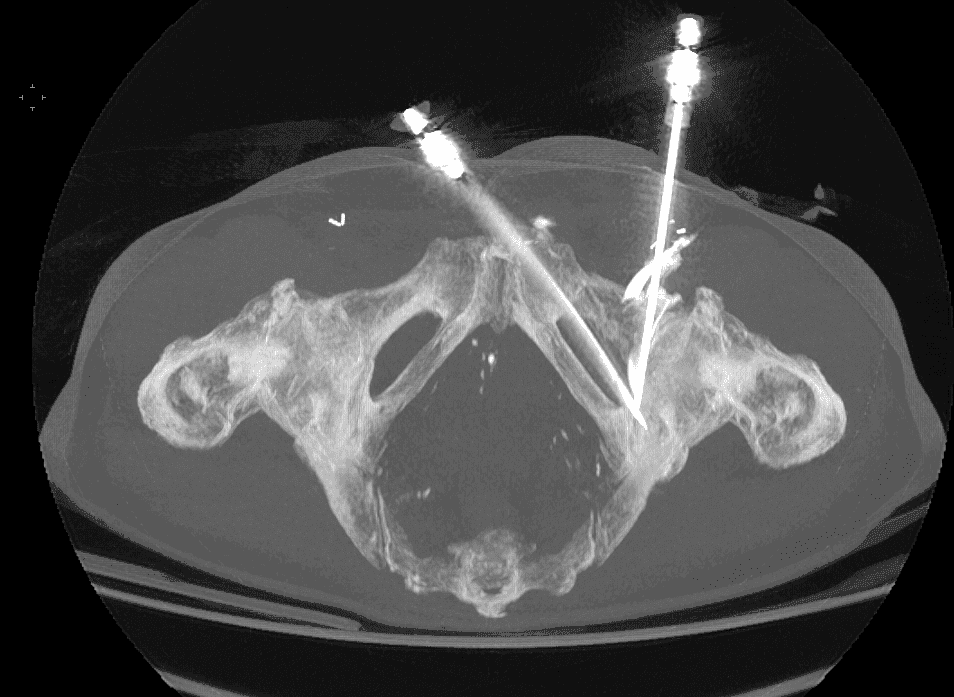

Installation du patient et guidage percutané :

Le patient est positionné de manière à faciliter l’accès à la zone fracturée.

Sous anesthésie locale (parfois combinée à une légère sédation), une aiguille de guidage est introduite en se servant de la fluoroscopie pour vérifier en continu sa progression.

Insertion et déploiement du matériel d’ostéosynthèse :

Une fois l’aiguille positionnée, le vissage est réalisé en respectant la trajectoire prédéfinie, permettant de réaligner les fragments osseux.

Le vissage est ensuite fixé de manière à assurer une stabilité mécanique suffisante pour supporter les contraintes de la zone cotyloïdienne.